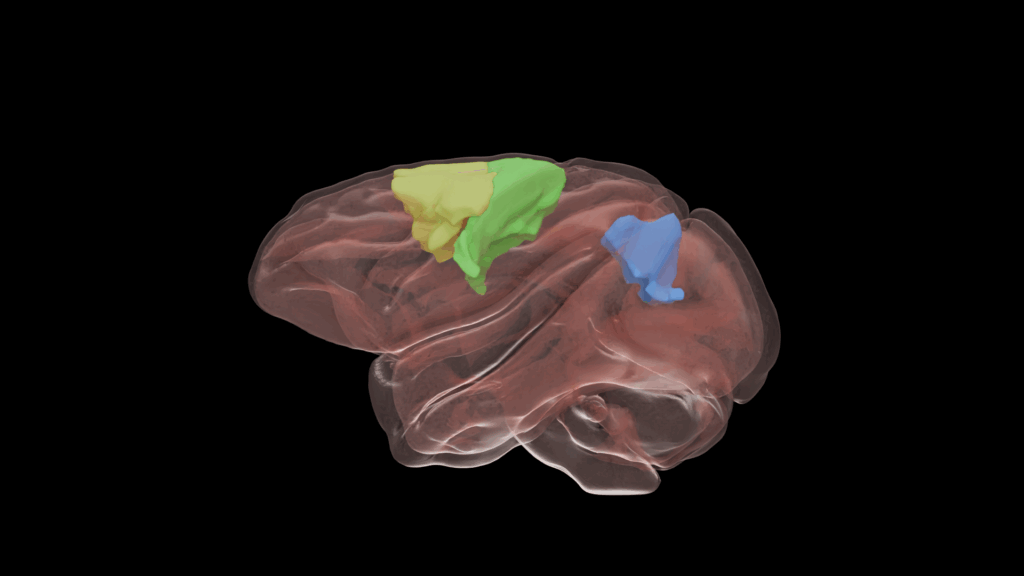

Um sich diesen Fragen zu nähern, untersuchten die Forschenden das motorische Lernen in den Hirnregionen von Rhesusaffen, die für die Steuerung von Arm- und Greifbewegungen verantwortlich sind. Die frontalen Areale sind unter anderem für die Planung und Ausführung von Bewegungen durch das Senden der entsprechenden Signale an die Muskeln verantwortlich. Parietale Hirnregionen spielen eine Schlüsselrolle bei der Integration sensorischer, insbesondere visueller Signale und helfen somit beispielsweise die Position des Bewegungsziels im Raum zu bestimmen.

Bild 1

Grafische Darstellung eines Rhesusaffen-Gehirns. Farbig sind die Hirnareale markiert, die für die Steuerung von Arm- und Greifbewegungen eine Rolle spielen. gelb: prämotorische Rinde, grün: motorische Rinde, blau: mediales intraparietales Areal. Quelle: Vladyslav Ivanov, Copyright: Deutsches Primatenzentrum GmbH